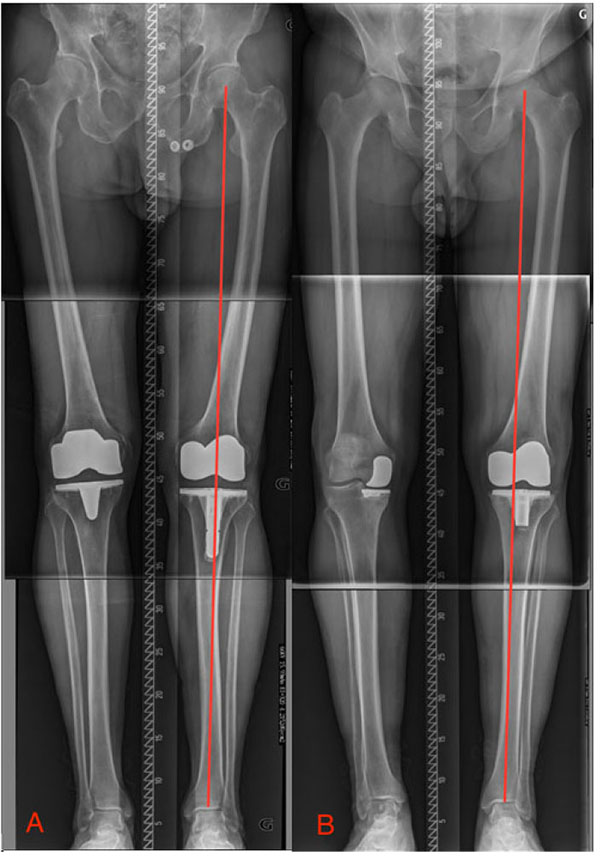

From boneandjoint.org.uk

The radiological assessment of total and knee Difference Between Unicompartmental And Total Knee Replacement The aim was to determine if this. A partial or unicondylar knee replacement, as its name suggests, replaces only the affected compartment of the knee. In unicompartmental knee replacement (also called partial knee replacement) only a portion of the knee is resurfaced with metal and plastic components. On the other hand, a total knee replacement involves the replacement of all. Difference Between Unicompartmental And Total Knee Replacement.

The radiological assessment of total and knee Difference Between Unicompartmental And Total Knee Replacement When should a surgeon opt for unicompartmental knee arthroplasty (uka) versus total knee arthroplasty (tka) to treat knee osteoarthritis (oa)? A partial or unicondylar knee replacement, as its name suggests, replaces only the affected compartment of the knee. On the other hand, a total knee replacement involves the replacement of all three compartments of the knee. Total knee arthroplasty (tka). Difference Between Unicompartmental And Total Knee Replacement.